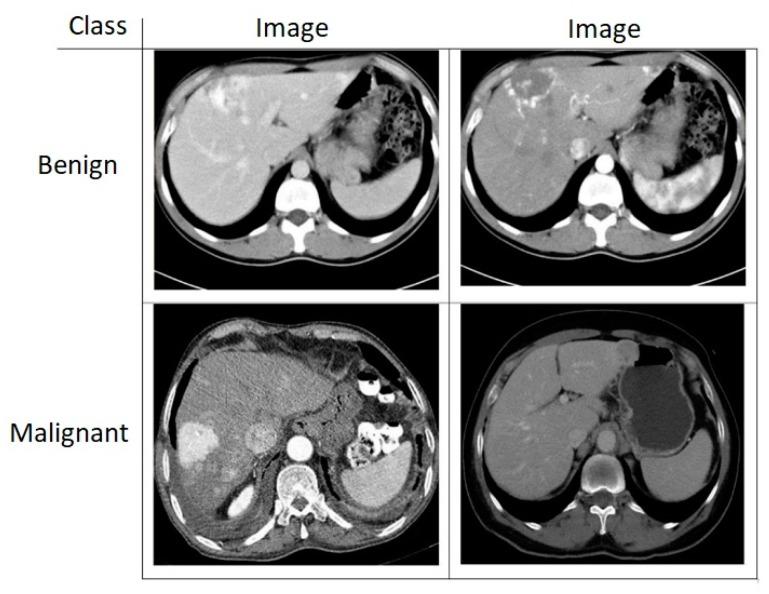

Rapid classification of tumors that are detected in the medical images is of great importance in the early diagnosis of the disease. In this paper, a new liver and brain tumor classification method is proposed by using the power of convolutional neural network (CNN) in feature extraction, the power of discrete wavelet transform (DWT) in signal processing, and the power of long short-term memory (LSTM) in signal classification. A CNN-DWT-LSTM method is proposed to classify the computed tomography (CT) images of livers with tumors and to classify the magnetic resonance (MR) images of brains with tumors. The proposed method classifies liver tumors images as benign or malignant and then classifies brain tumor images as meningioma, glioma, and pituitary. In the hybrid CNN-DWT-LSTM method, the feature vector of the images is obtained from pre-trained AlexNet CNN architecture. The feature vector is reduced but strengthened by applying the single-level one-dimensional discrete wavelet transform (1-D DWT), and it is classified by training with an LSTM network. Under the scope of the study, images of 56 benign and 56 malignant liver tumors that were obtained from Fırat University Research Hospital were used and a publicly available brain tumor dataset were used. The experimental results show that the proposed method had higher performance than classifiers, such as K-nearest neighbors (KNN) and support vector machine (SVM). By using the CNN-DWT-LSTM hybrid method, an accuracy rate of 99.1% was achieved in the liver tumor classification and accuracy rate of 98.6% was achieved in the brain tumor classification. We used two different datasets to demonstrate the performance of the proposed method. Performance measurements show that the proposed method has a satisfactory accuracy rate at the liver tumor and brain tumor classifying.

快速分类在医学图像中检测到的肿瘤在疾病的早期诊断中非常重要。在本文中,通过使用卷积神经网络(CNN)在特征提取、离散小波变换(DWT)在信号处理、长短期记忆(LSTM)在信号分类中的能力,提出了一种新的肝脑肿瘤分类方法。提出了一种 CNN-DWT-LSTM 方法,用于对有肿瘤的 CT 肝脏图像进行分类,对有肿瘤的磁共振(MR)脑图像进行分类。所提出的方法将肝肿瘤图像分类为良性或恶性,然后将脑肿瘤图像分类为脑膜瘤、神经胶质瘤和垂体瘤。在混合 CNN-DWT-LSTM 方法中,从预先训练的 AlexNet CNN 架构获得图像的特征向量。通过应用单级一维离散小波变换(1-D DWT)对特征向量进行降维和增强,然后通过 LSTM 网络进行训练进行分类。在研究范围内,使用了来自 Firat 大学研究医院的 56 个良性和 56 个恶性肝肿瘤的图像和一个公开可用的脑肿瘤数据集。实验结果表明,与 K 最近邻(KNN)和支持向量机(SVM)等分类器相比,所提出的方法具有更高的性能。通过使用 CNN-DWT-LSTM 混合方法,在肝肿瘤分类中达到了 99.1%的准确率,在脑肿瘤分类中达到了 98.6%的准确率。我们使用了两个不同的数据集来证明所提出方法的性能。性能测量表明,所提出的方法在肝肿瘤和脑肿瘤分类中具有令人满意的准确率。